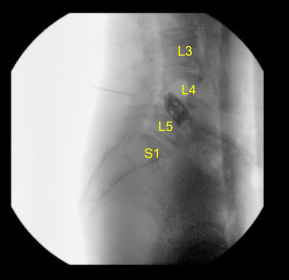

La región lumbar se preparó y cubrió de la manera estéril habitual y luego se empleó una fluoroscopia para localizar nuestra incisión, que se trazó con un marcador indeleble en la línea media de la región lumbar que recubre el interespacio L4-L5. Se dosificaron antibióticos intravenosos y se completó una llamada al orden.

Retiramos el tejido blando del hueso de una manera no traumática y luego aplicamos el sistema de retractor McCullough. Luego se utilizaron los retractores Gelpi en ángulo recto para mantener separados la piel y los bordes musculares. Utilizamos la fluoroscopia una vez más para localizar nuestro nivel de operación.

Se fijó una broca de 3 mm al taladro eléctrico y se utilizó para crear laminectomías anchas en el nivel L4/5 y laminotomías bilateralmente. Una vez que se encontró el ligamento flavum, utilizamos punzones de Kerrison bilateralmente para eliminar los fragmentos óseos adicionales y para completar facetectomías mediales y foraminotomías.